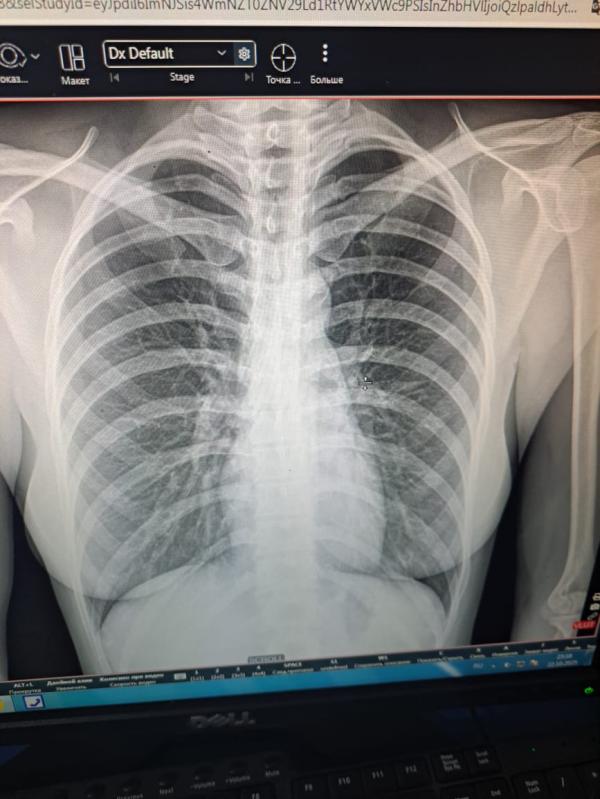

Как читать медицинские снимки: советы и расшифровка

Кто умеет читать снимок?